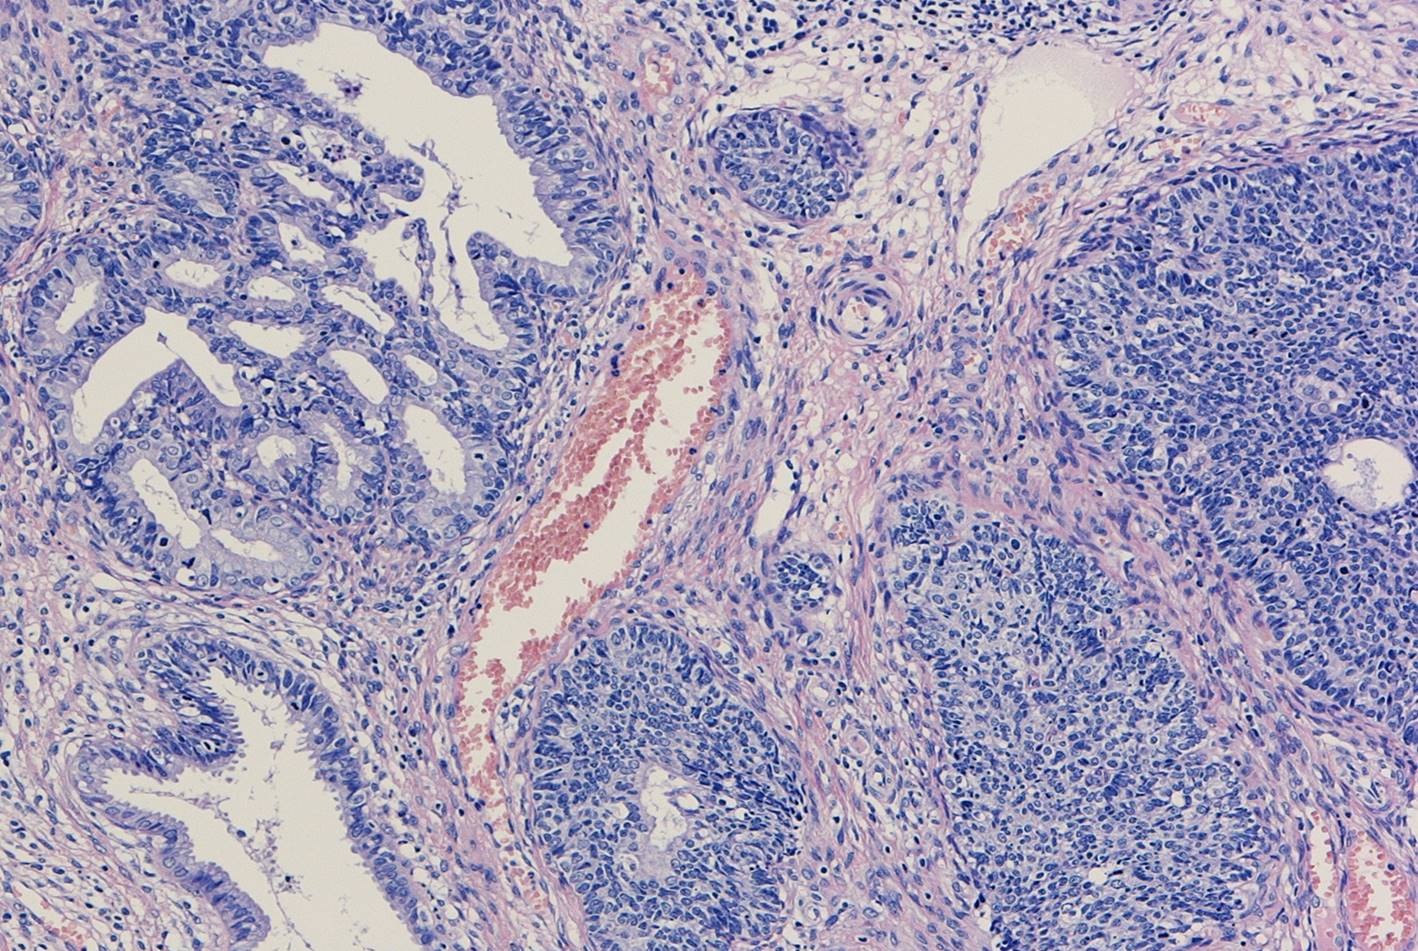

子宮頸部のSCJにおいてクロマチン増量を示す異型上皮が明瞭な

腺管構造や充実性胞巣構造を形成し増生していた。充実性増生を示す成分はN/C比や核分裂像が目立ち、免疫染色ではsynaptophysin、chromogranin A、CD56が陽性であり神経内分泌分化が示唆された。以上の所見より、神経内分泌癌成分を伴う腺癌と診断された。面積的には腺癌成分が8割で神経内分泌癌成分は2割であった。腺癌成分で微小浸潤がみられたが神経内分泌癌成分はin situであった。

腺管構造や充実性胞巣構造を形成し増生していた。充実性増生を示す成分はN/C比や核分裂像が目立ち、免疫染色ではsynaptophysin、chromogranin A、CD56が陽性であり神経内分泌分化が示唆された。以上の所見より、神経内分泌癌成分を伴う腺癌と診断された。面積的には腺癌成分が8割で神経内分泌癌成分は2割であった。腺癌成分で微小浸潤がみられたが神経内分泌癌成分はin situであった。